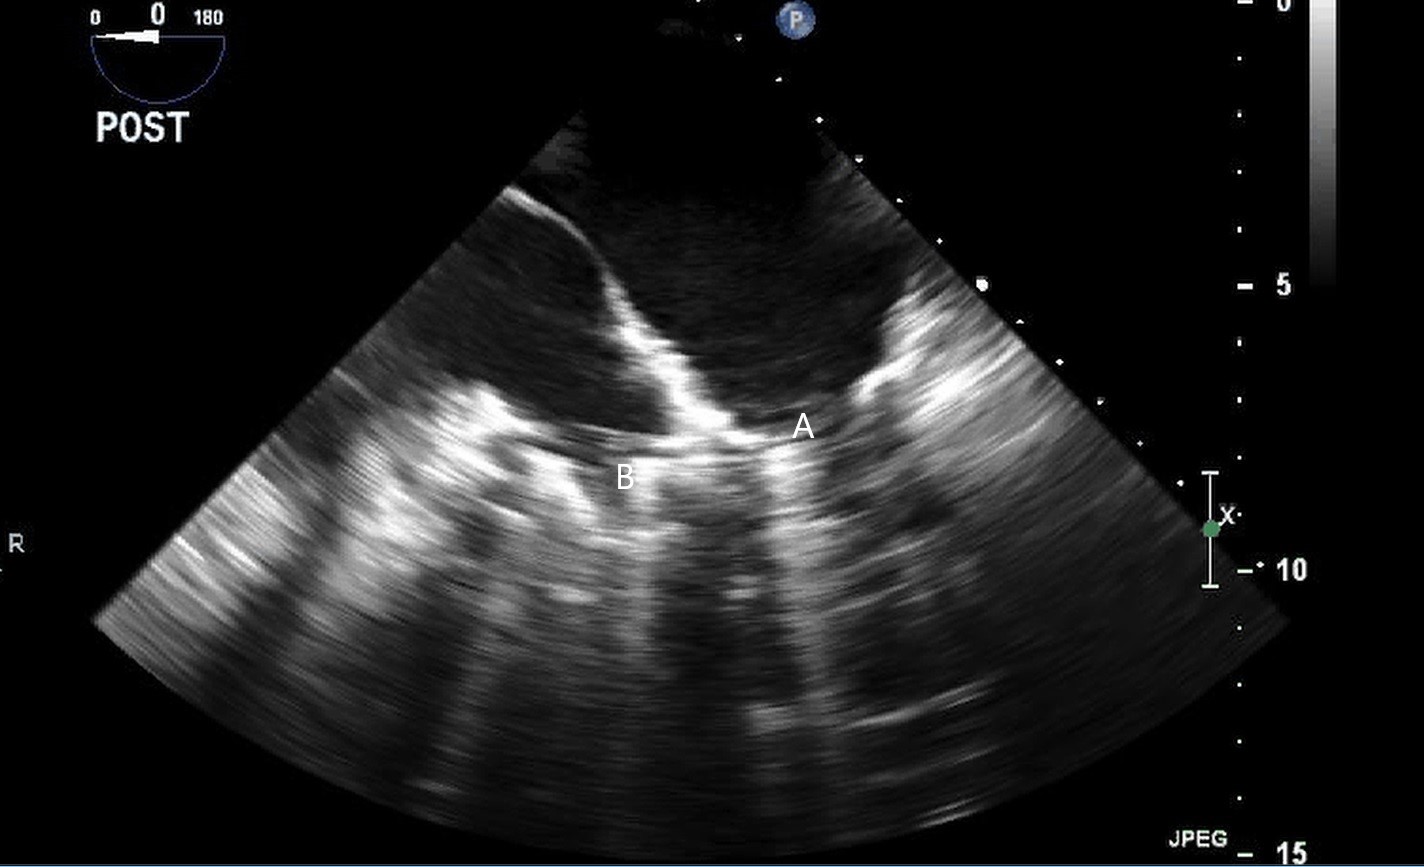

Impella (A) in the LV cavity caused disruption and damage to subvalvular apparatus resulting in flail segment (B) of the mitral valve.

Fig. 4.Impella (A) placement causing disruption and damage to subvalvular apparatus resulting in mitral valve flail (B) and mitral regurgitation (C).